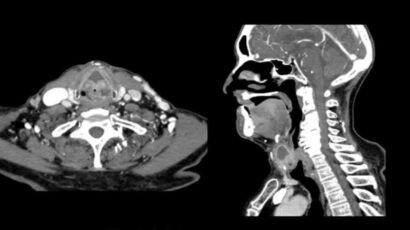

Un examen de tomografía axial computarizada (TAC) cervical es una herramienta de diagnóstico por…

El examen TAC cervical es una herramienta médica importante que ayuda en el diagnóstico…

El TAC cervical, o tomografía axial computarizada cervical, es una técnica de imagen médica…